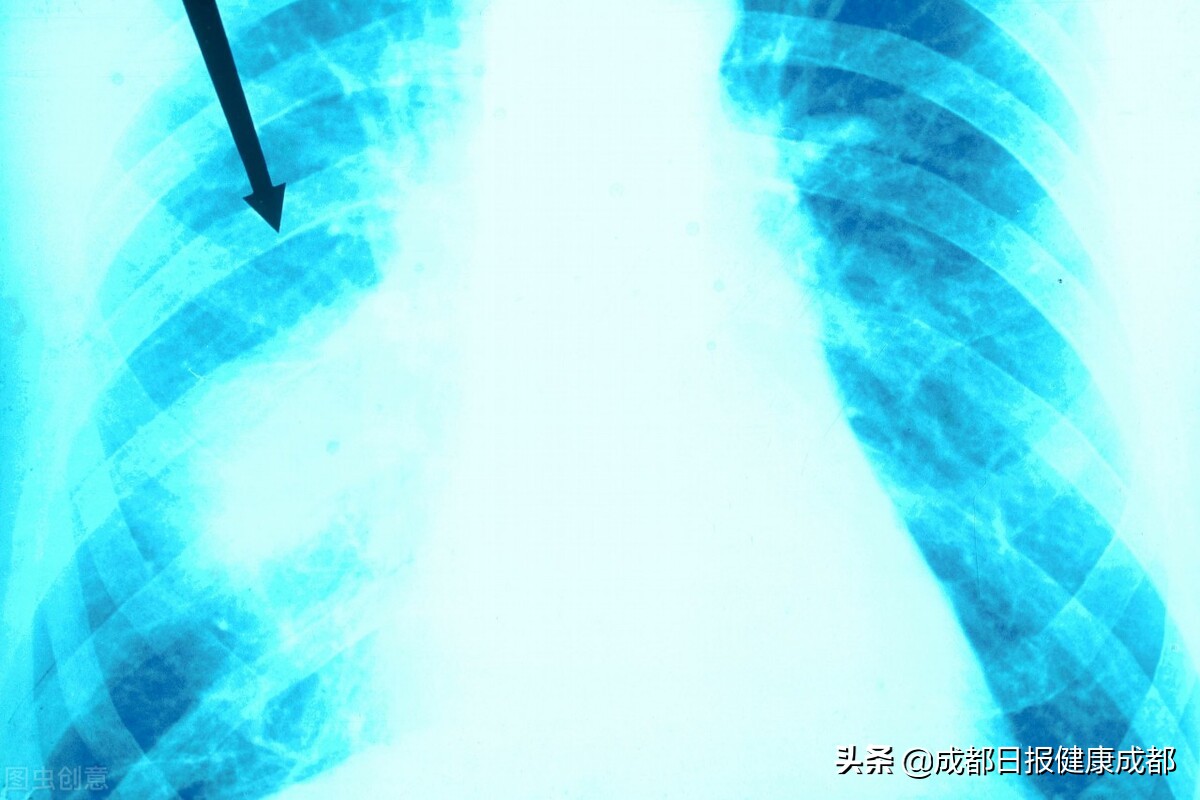

从半年前开始,46岁的张先生(化名)出现间断咳嗽、咳痰,辗转省内多家医院不见好转。期间他进行了两次电子支气管镜、十余次胸部CT等各种检查,仍无法确诊是何种病症。张先生的女儿是一名护士,在她的强烈建议下,张先生来到了成都市第二人民医院就诊。未曾想到,正是在这里,隐藏很深的肺腺癌被“挖”了出来,幸好,肺癌还没有转移。

专家说,张先生之前的两次电子支气管镜检查也没有阳性发现,这可能与未能精准取到病变组织或病理取材较少,不能满足诊断所需有关。如何精准定位并获取足够肺病变组织成了首要难题。